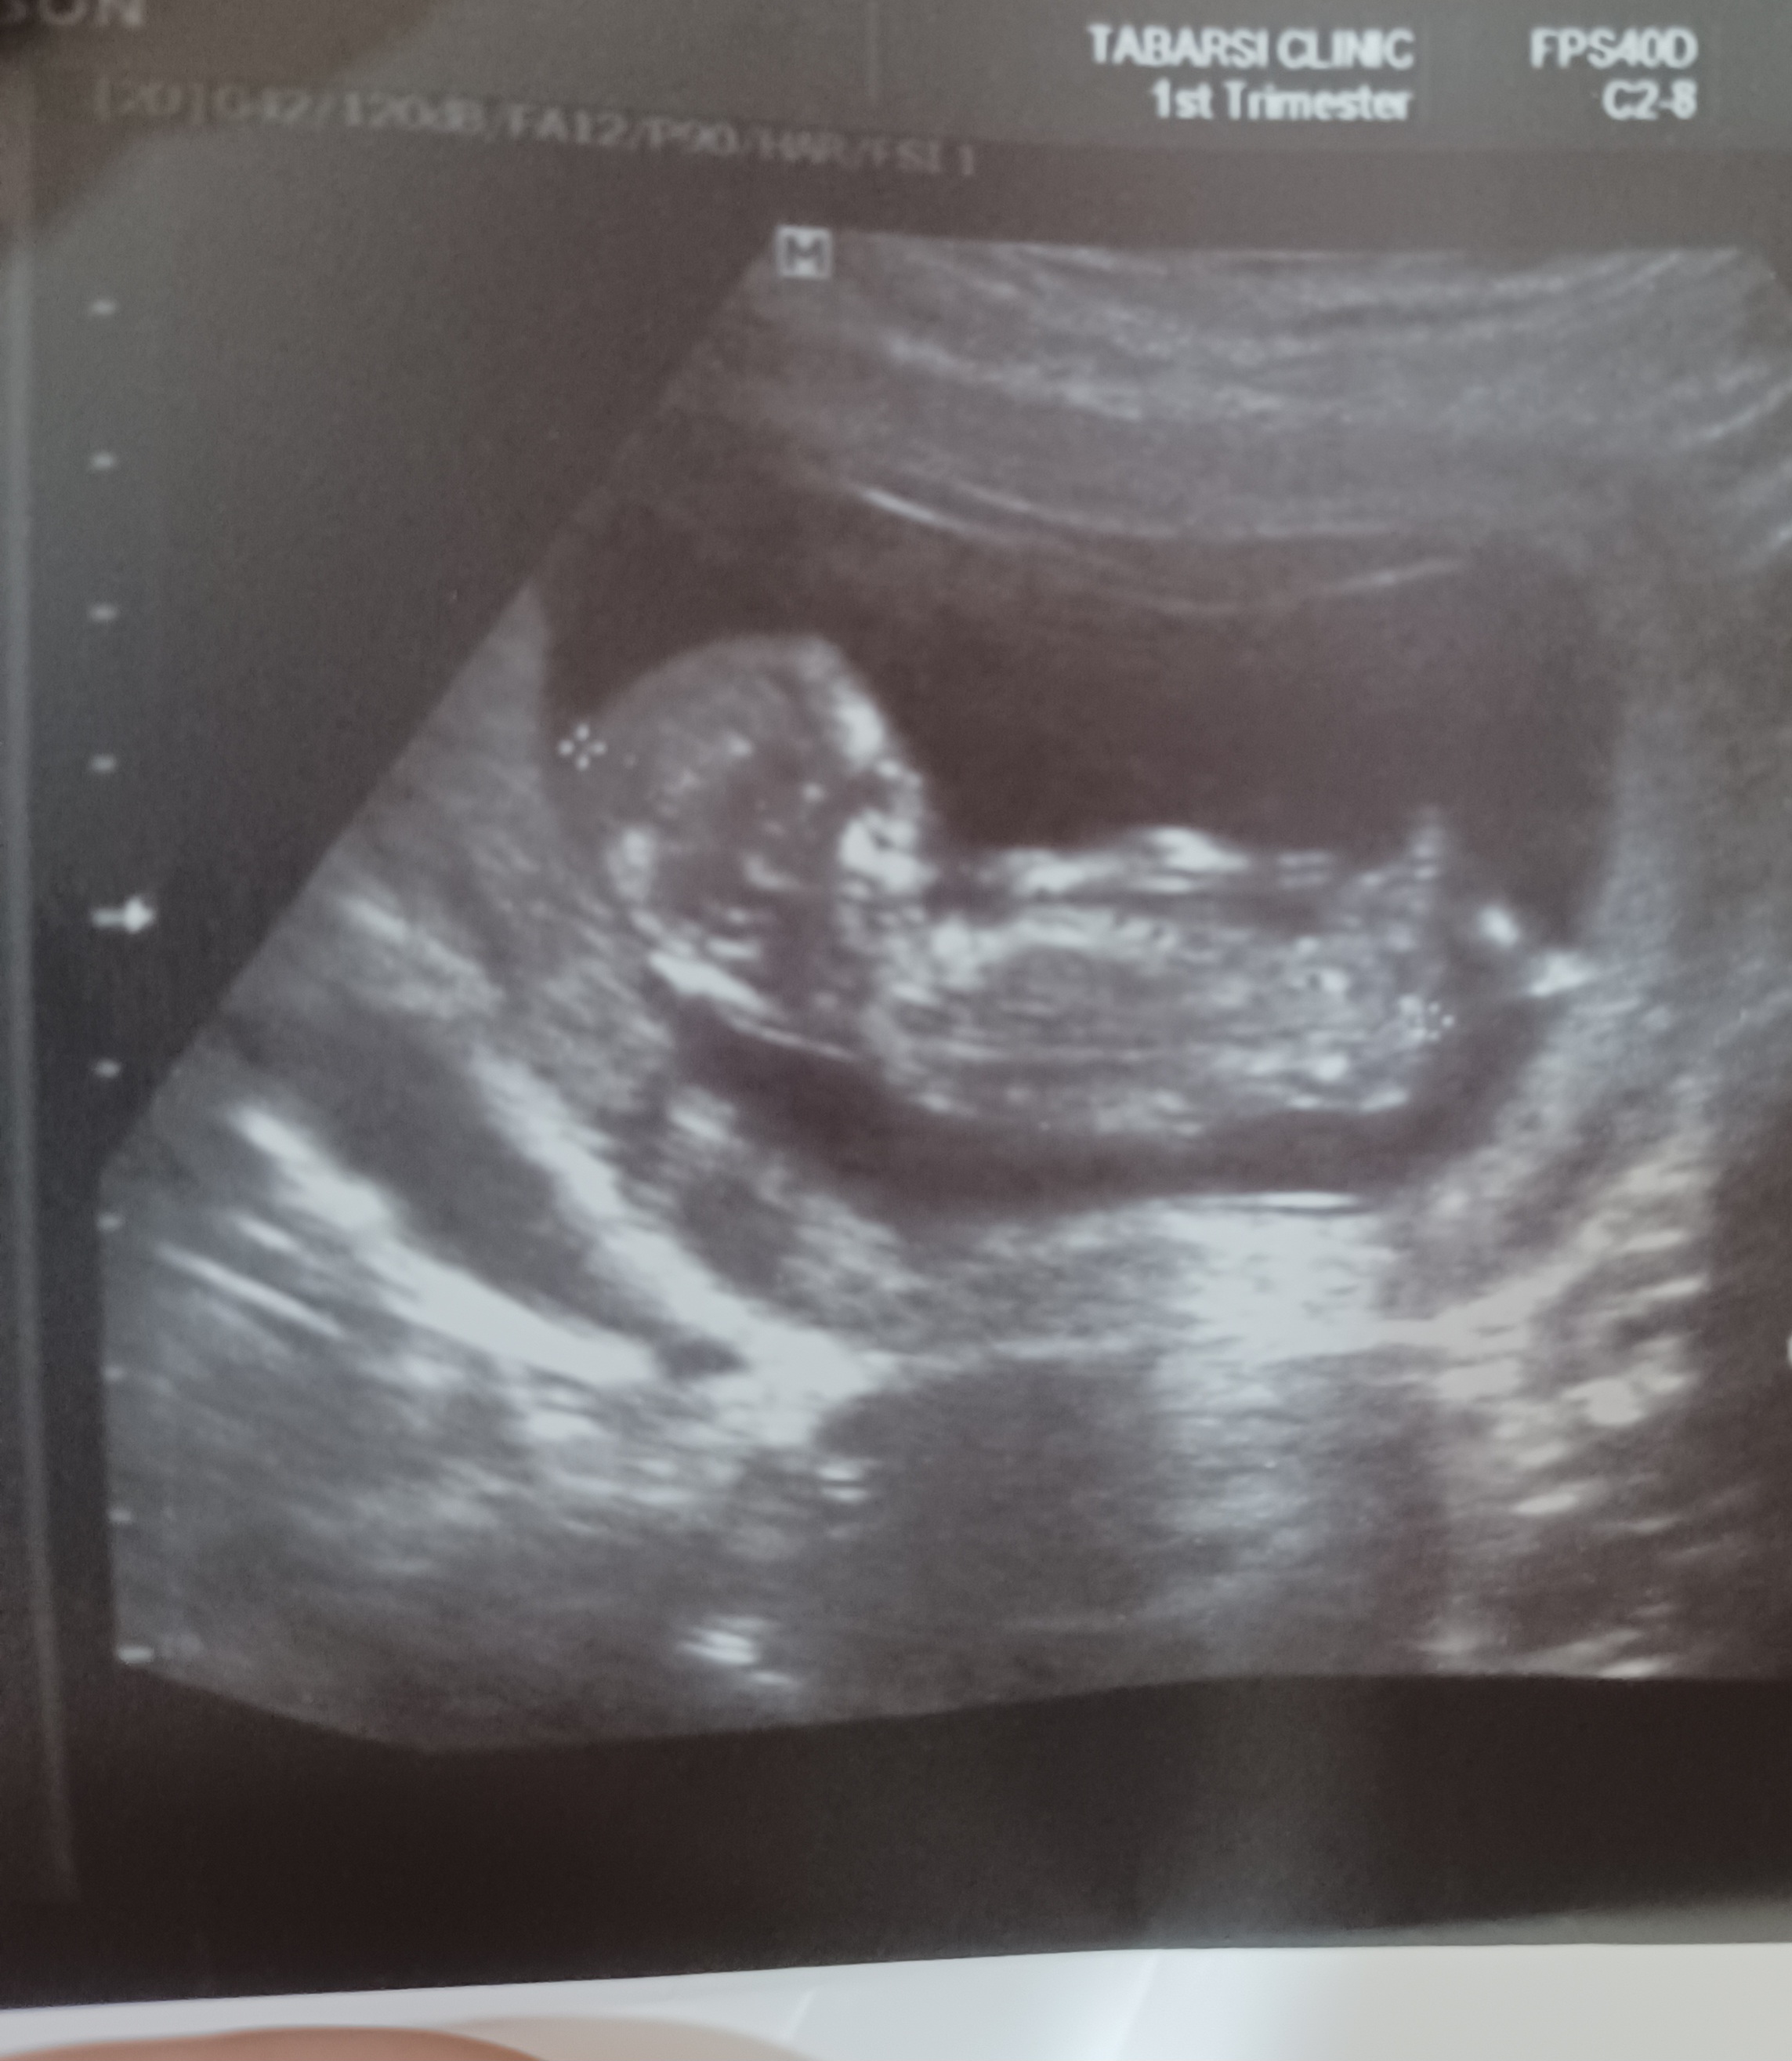

بلدی😍 این ان تیاینم سونو قلب

ای خدا گل دختره؟😍

ضربان قلبش چندبود؟

فقط 10 هفته و 6 روز به تولد باقی مونده !